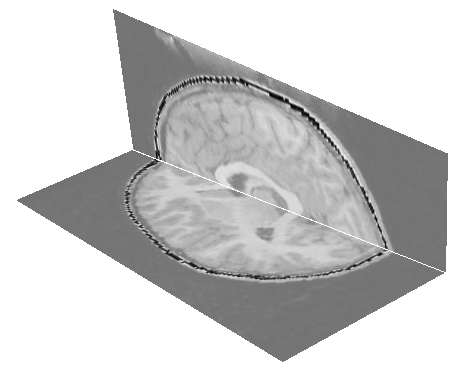

HingeSlicer: Volume Image Exploration Using Extended 3D Slice Plane Widgets, T. McInerney and S. Broughton, Graphics Interface, Quebec City, CA, June 2006, pages 171-178. |

Sketch-Line Interactions for 3D Image Visualization and Analysis, T. McInerney and Y.S. Shih, 9th International Symposium on Visual Computing (ISVC 2012), Rethymnon, Crete, Greece, Jul. 2012, pages 686-697. |